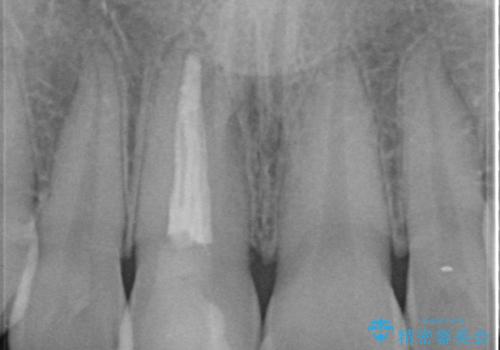

- 前歯の見た目の改善を求めて来院されました。

ジルコニアクラウンによる審美性の改善を計画します。

失活歯のため捻転を改善し、根管治療は特に希望されなかったのでそのままとしました。

今回失活歯であったため捻転を取り反対側の前歯に揃えて補綴を行うことができました。